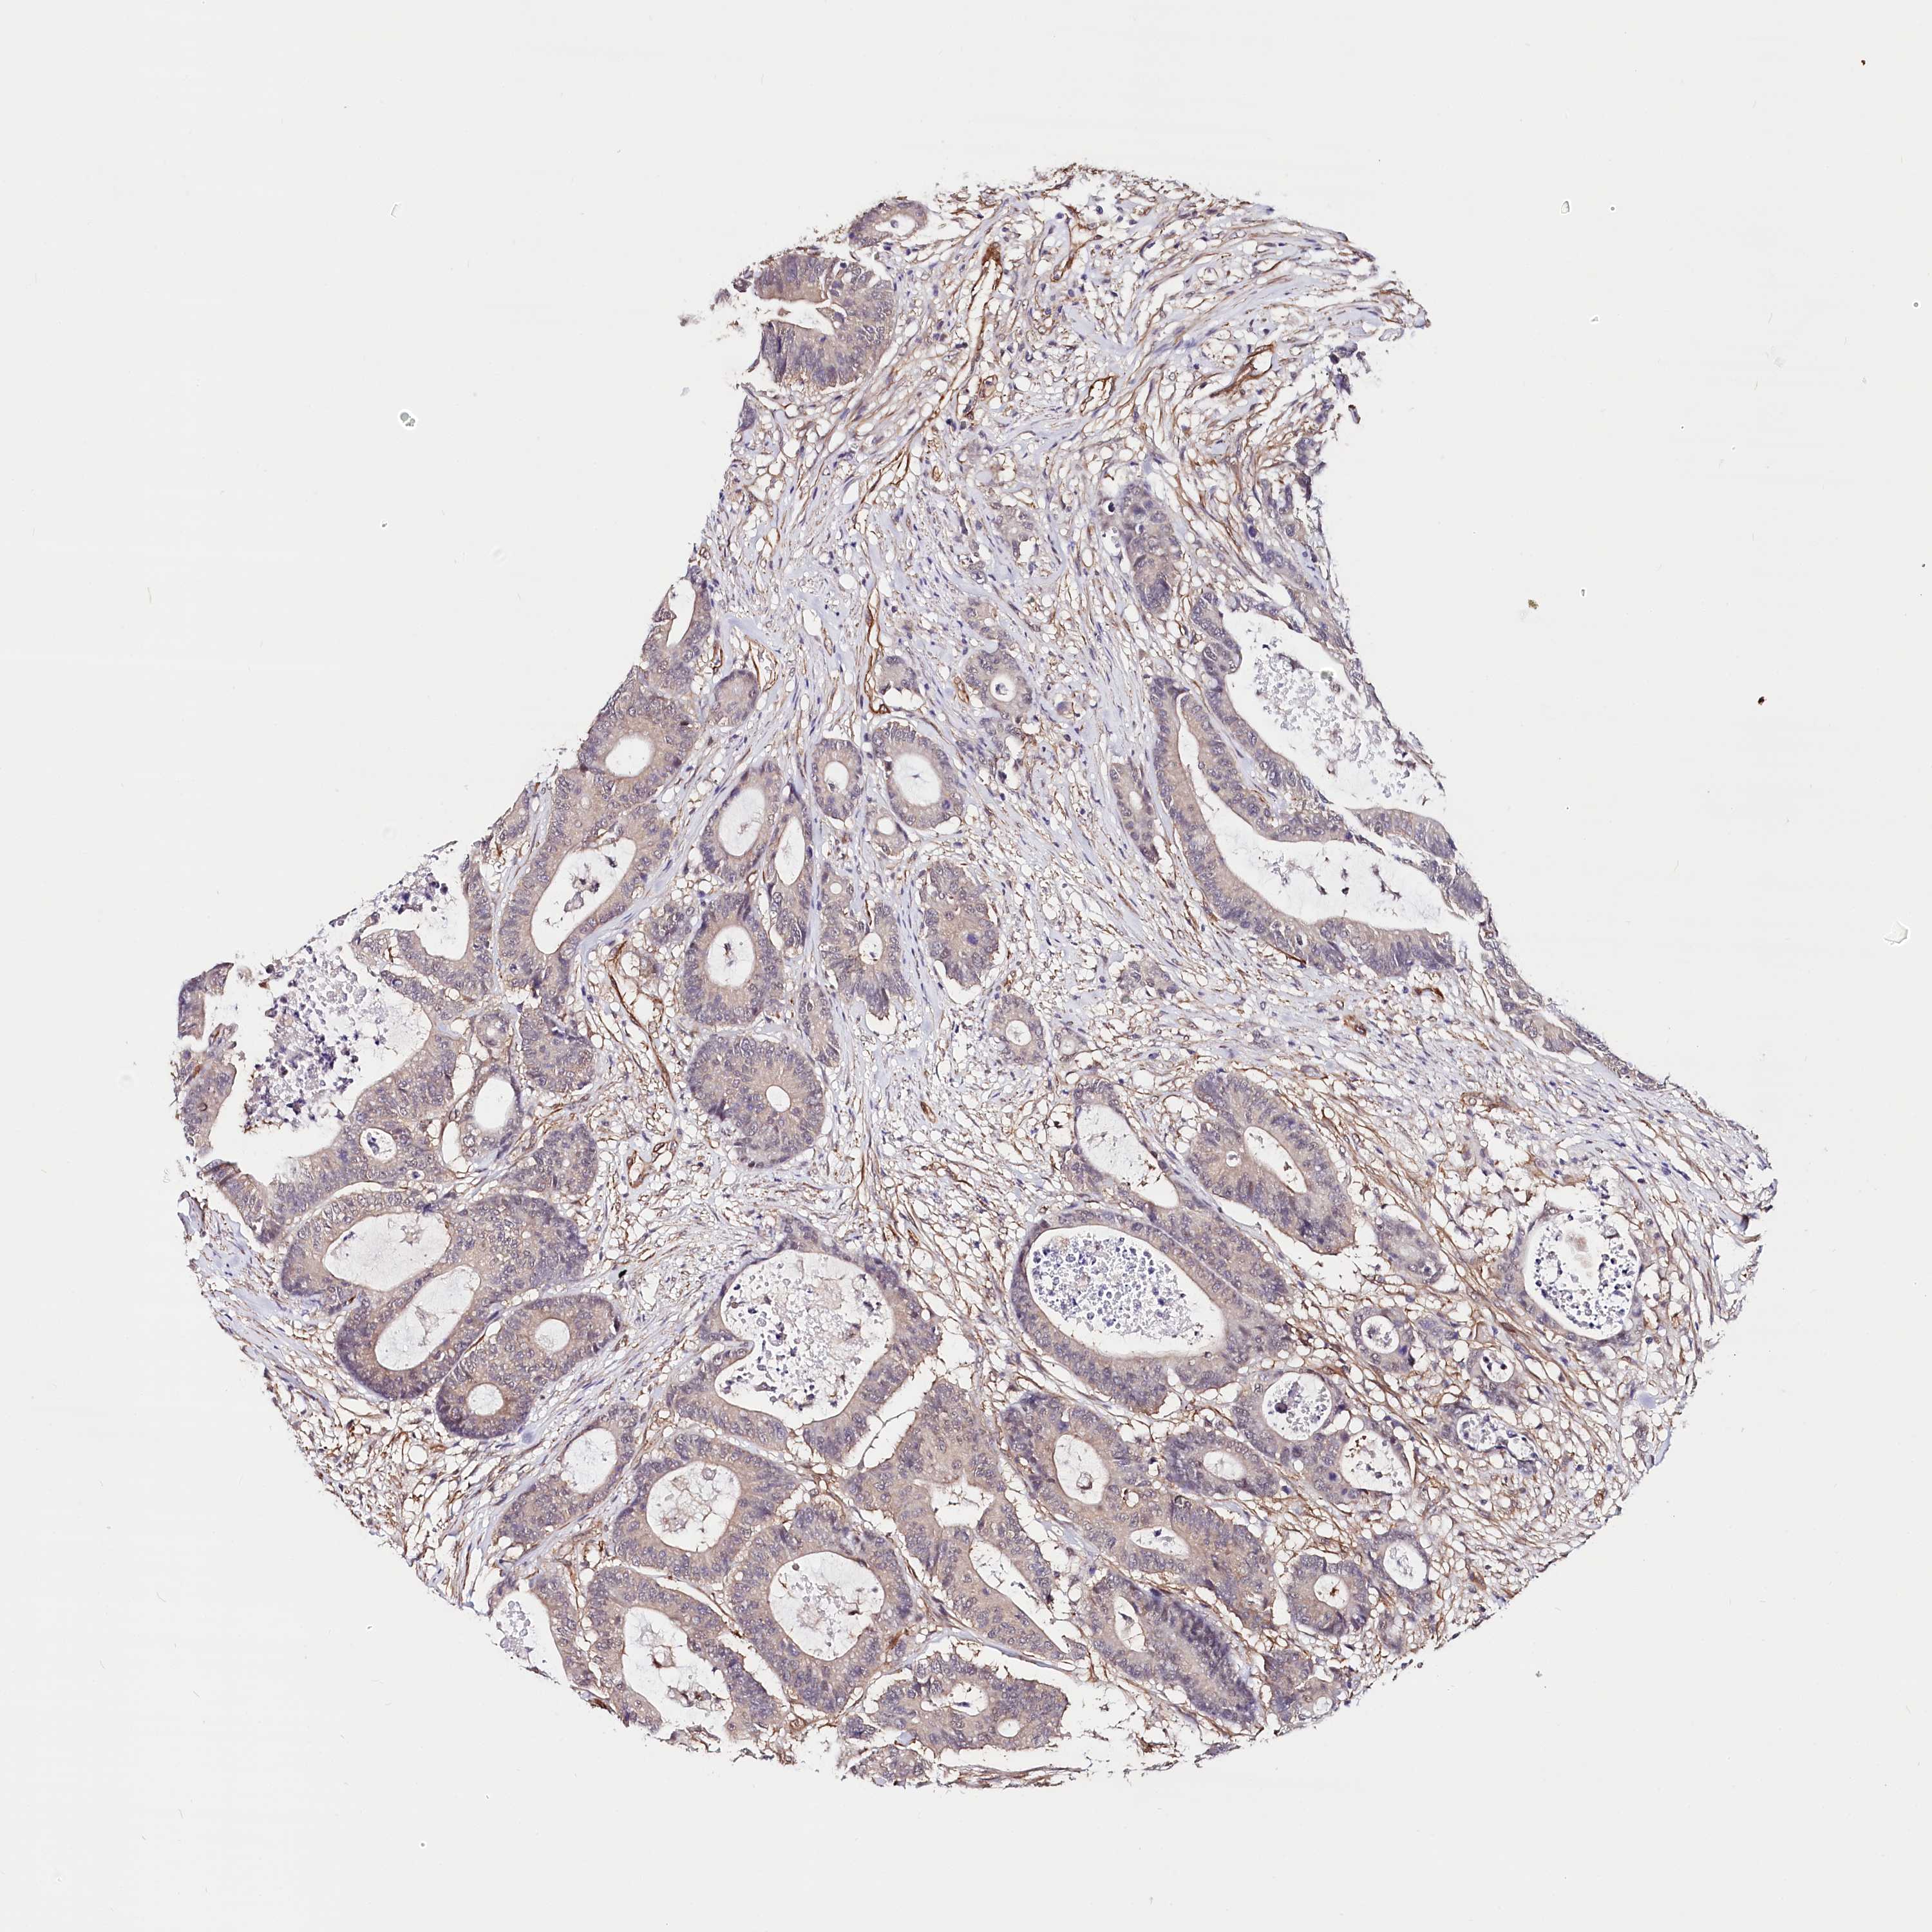

Colorectal cancer

Rectum adenocarcinoma

Average pTPM 10.2

Number of samples 88